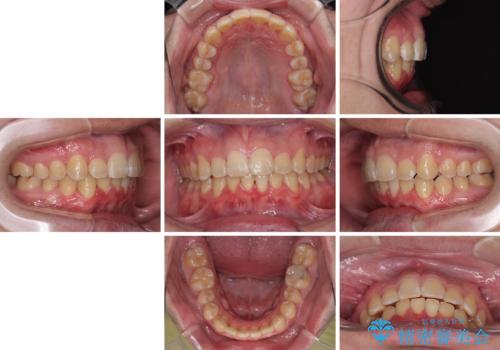

上顎前歯のデコボコを改善してスッキリした口元に ワイヤー装置での非抜歯矯正

上下前歯にデコボコがありましたが、特に上顎の叢生が強く、通常に歯列を整えると、上顎が前方に突出し、口元の突出感が残った仕上がりとなる可能性が考えられました。

非常に咬合力が強く、左側の臼歯がなかなか後方へ移動できなかったのですが、2年ほどかけて大変満足のいく仕上がりを達成することができました。